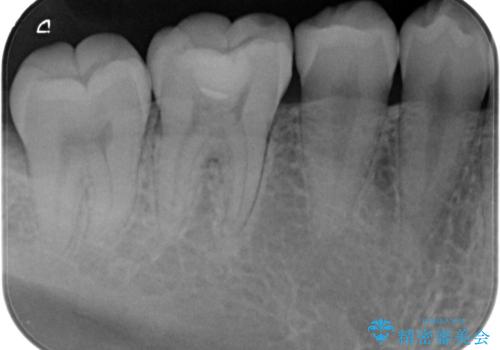

歯と歯の間に虫歯(コンタクトカリエス)がありましたので、拡大鏡下で虫歯を取り、白い詰め物(e-maxインレー)で治療を行いました。